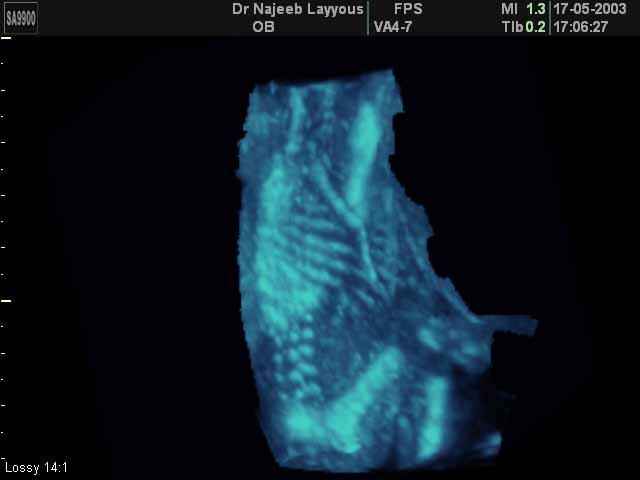

- Fetal Skeleton Ultrasound Photos